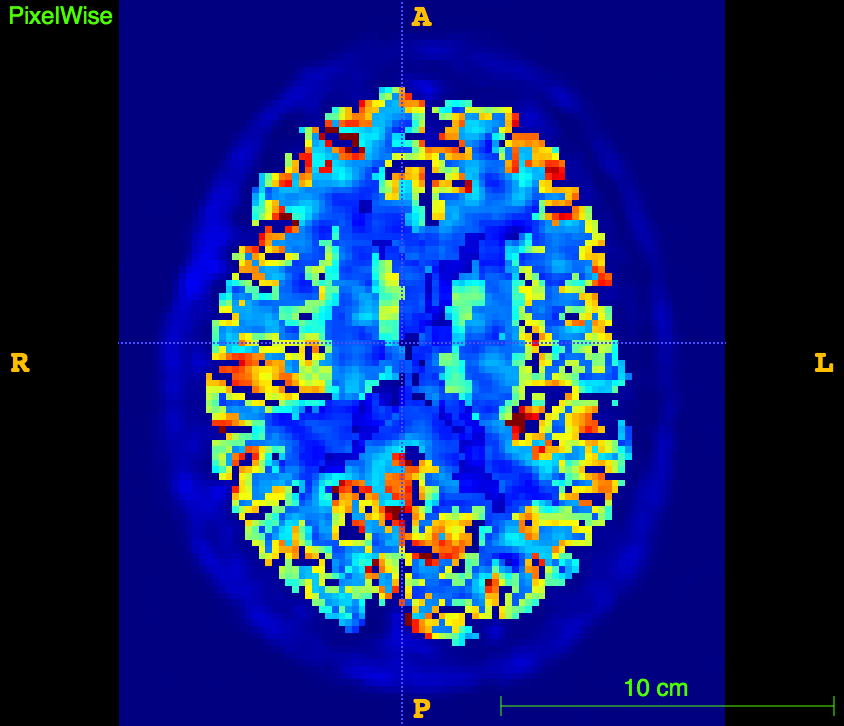

Glucose PET/MRI in MS

29 patients, 14 CIS/eRRMS and 15 RRMS underwent a PET/MRI with:

- MRI sequences: 3D T1, 3D FLAIR, 3D DIR

- 18F-Fdg PET in list-mode

The aim is to study the relationship between:

- Cortical Thickness

- WM/GM lesion number/volume

- aMRGlu